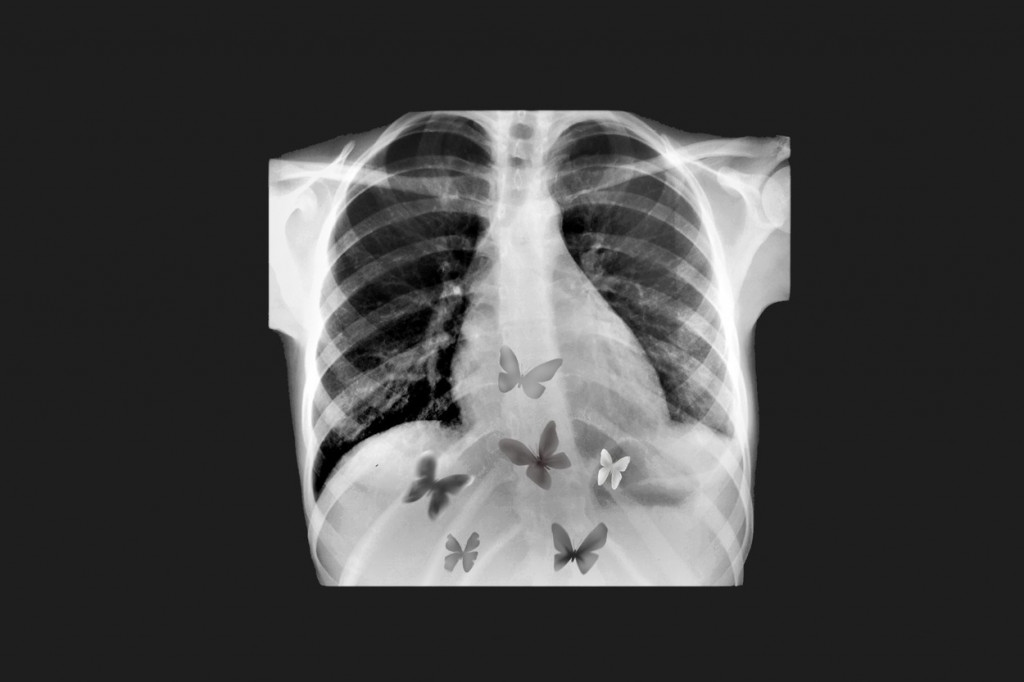

Sreća i ljubav se manifestuju u celom telu. Emocionalno uzbuđenje zbog osećanja radosti utiče na naše mišiće koji se nalaze u stomaku, crevima i bešici — otuda i značenje izraza „leptirići u stomaku“.

Međutim, u poređenju sa srećom, ljubav se nije toliko osećala u nogama. Obe emocije takođe oslobađaju dopamin i serotonin, hormone dobrog osećanja koji pomažu u regulisanju našeg raspoloženja i emocija. Ova dva neurotransmitera rade ruku pod ruku u održavanju hemijske ravnoteže za celo telo.